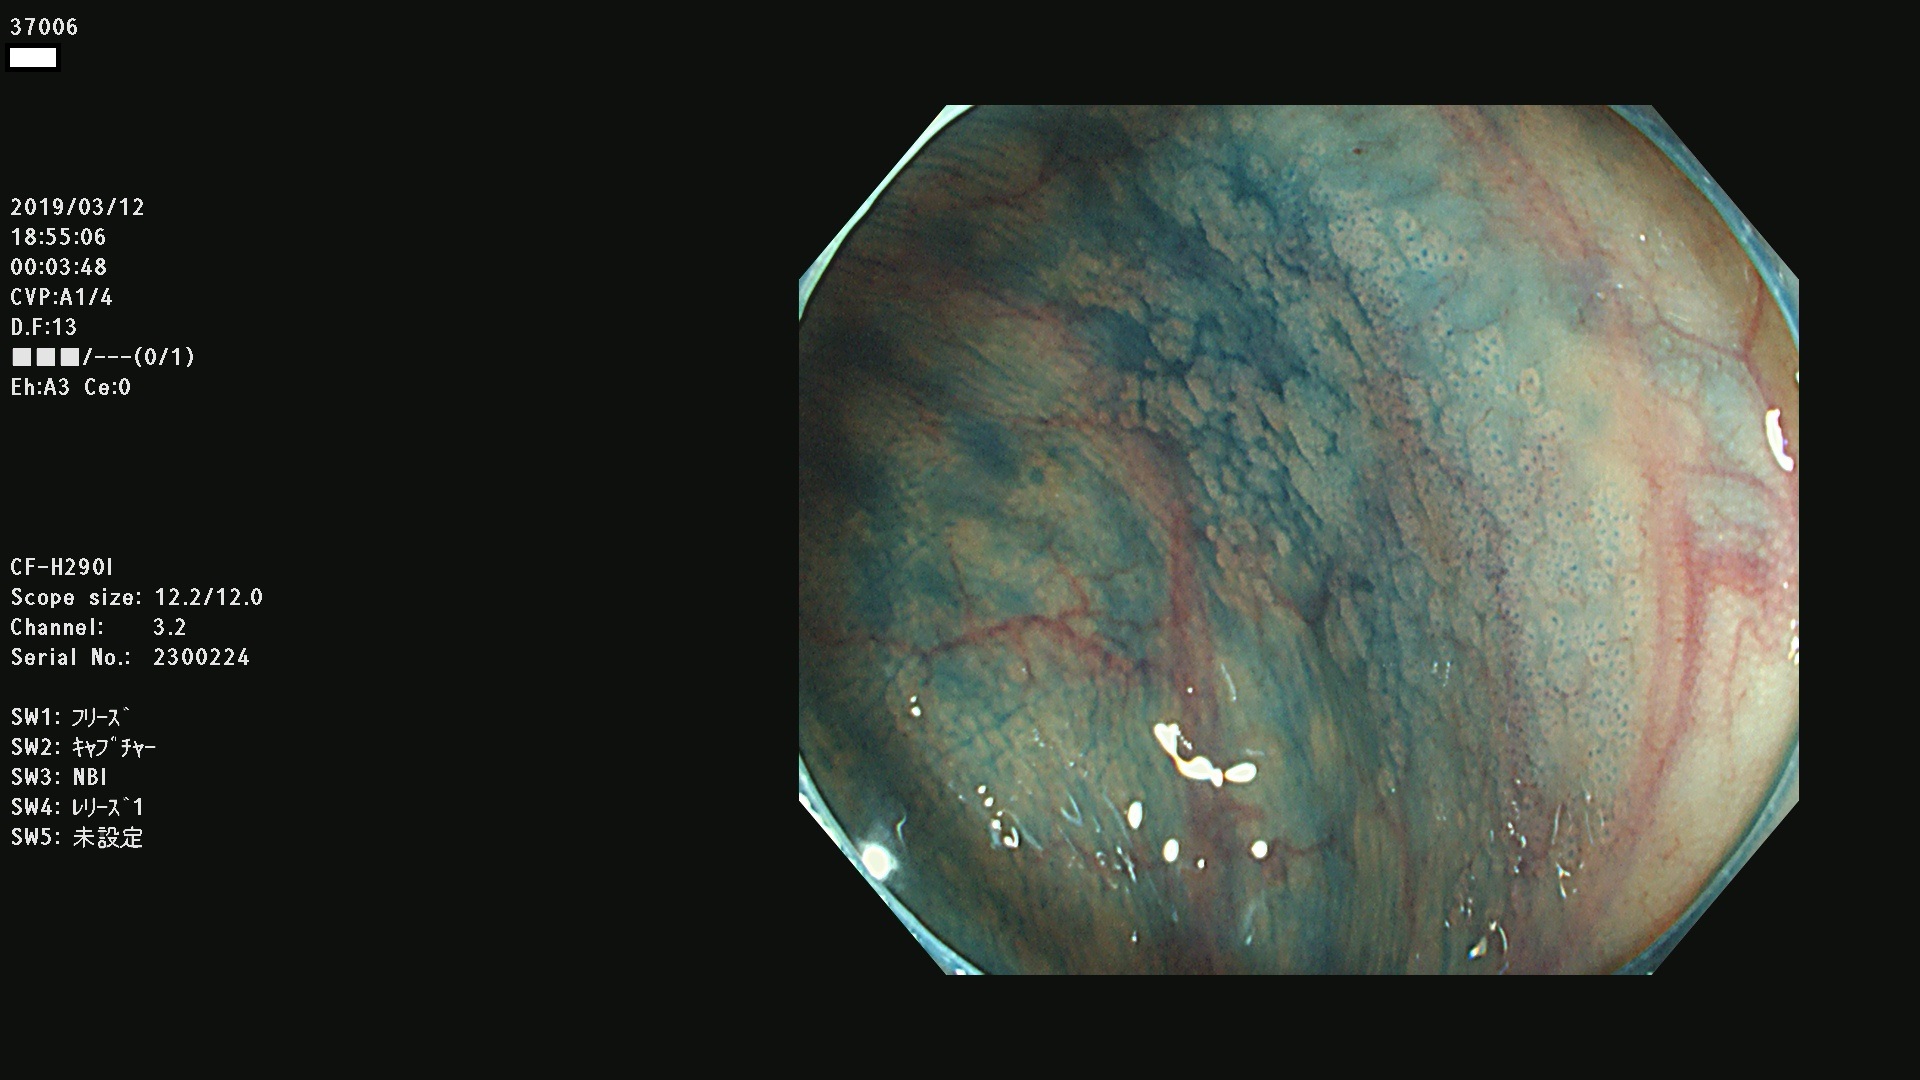

37000 37002 37004 37005 37006(SSAPのみ) 37007 37009 37013 37014 37015 37017(SSAPのみ) 37019 37020 37021 37022 37025 37026 37027 37028 37029 37031 37032 37033 37034 37035 37036 37037 37038 37041 37042 37043 37044 37045 37047 37051 37052 37053(SSAPのみ) 37055 37056 37058 37060 37061 37062 37063 37067 37072 37073 37074 37076 37077 37078 37079 37080 37081 37083 37084 37085(SSAPのみ) 37086 37087 37088 37089 37092 37093 37094 37095 37097 37098 3709

発見困難で危険性の高い平坦型病変(上記100名より抽出)